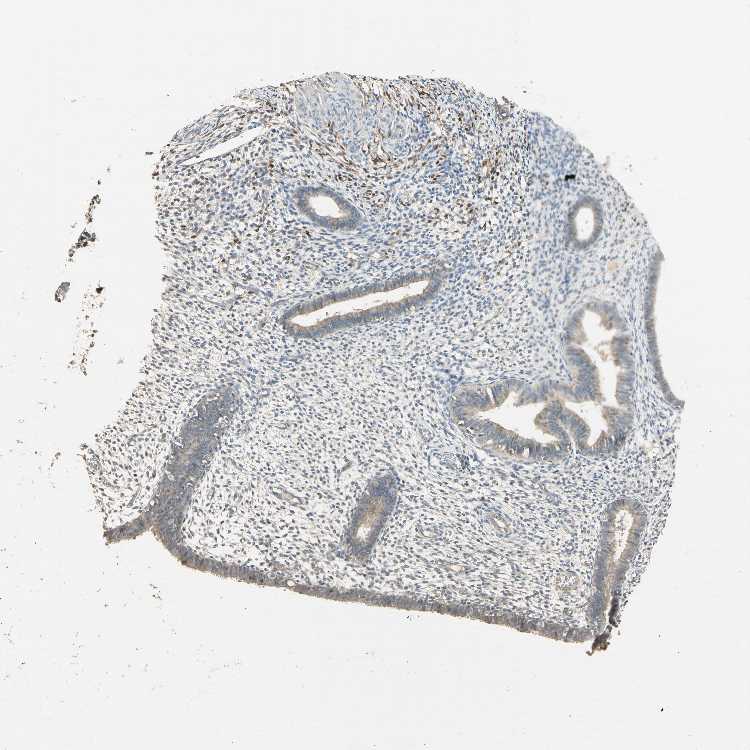

ENDOMETRIUM 1 - Antibody stainingi

Antibody staining in the annotated cell types in the current human tissue is reported as not detected, low, medium, or high, based on conventional immunohistochemistry profiling in selected tissues. This score is based on the combination of the staining intensity and fraction of stained cells.

Each image is clickable and will lead to virtual microscopy that enables deeper exploration of all samples and also displays staining intensity scores, fraction scores and subcellular localization as well as patient and tissue information for each sample.

Antibody HPA007045Antibody HPA027258

Cells in endometrial stroma Not detectedNot detected

Glandular cells Not detectedLow

ENDOMETRIUM 2 - Antibody stainingi

Glandular cells LowLow